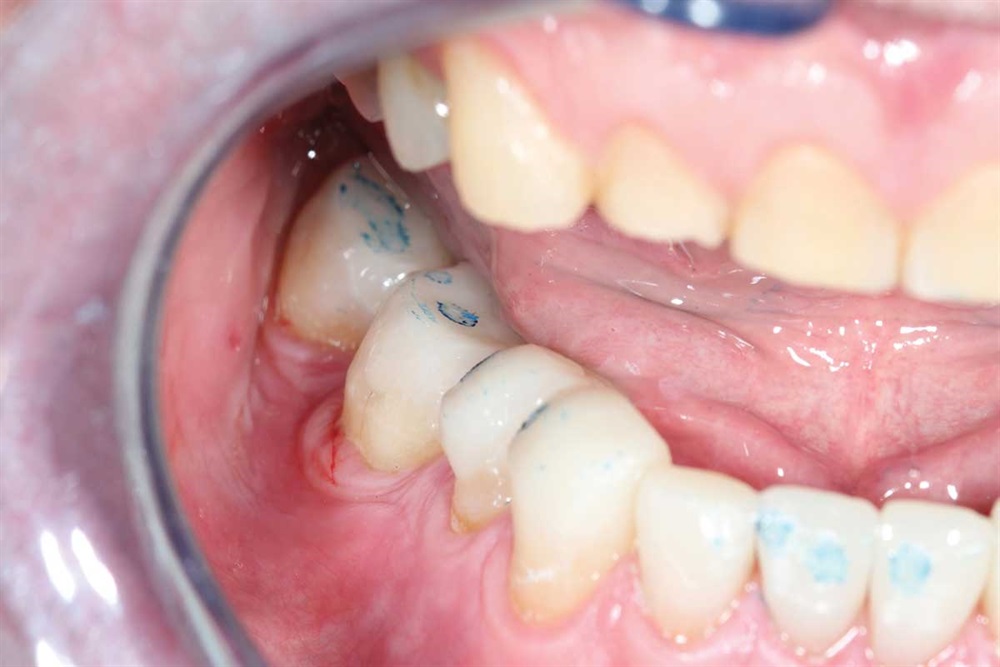

Fig. 42: Marks show heavier contact in lateral and protrusive excursions. Again, light occlusion on the centrals because of the lack of support I was bonding to.

Show Your Work